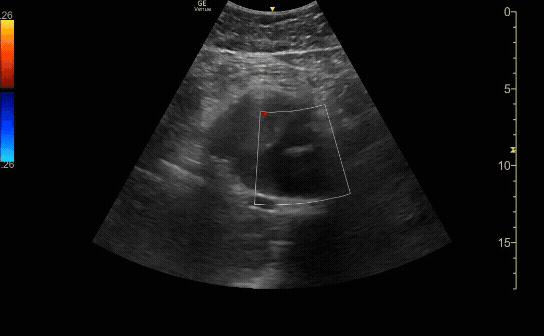

Proximal transverse (short) view of the aorta showing the celiac artery and SMA. Measure anterior-to-posterior proximally. Should measure <3cm.

c/o Taylor Wahrenbrock, MD